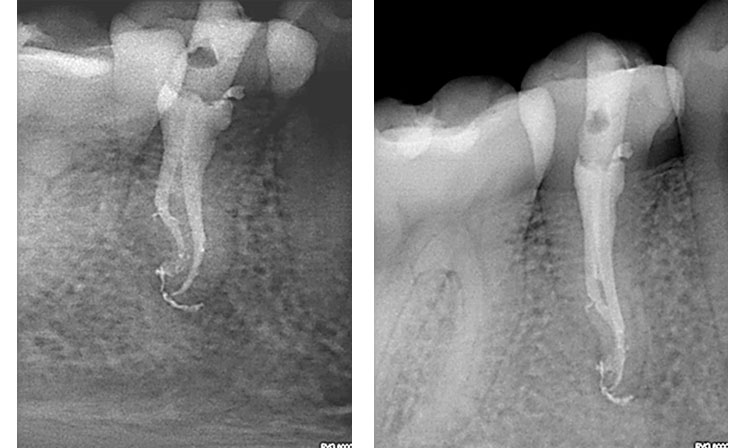

왼쪽 2개의 사진에서 치아가 2개 있는데요, 둘 중에 오른쪽 치아가 괴사된 치아입니다. 그리고 오른쪽 2개의 사진은 신경치료를 한 치아의 엑스레이 사진입니다.(출처: https://zarc4endo.com/)